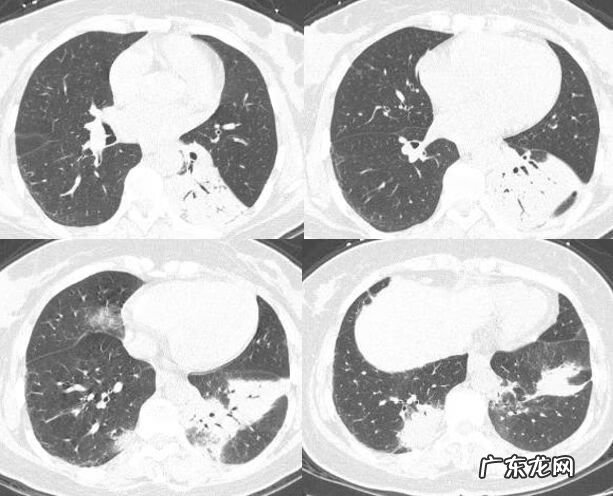

两者临床表现相似,NSIP主要表现为双侧对称性的磨玻璃密度影 。但是仔细看,对于NSIP来说,网格影和牵拉性支气管扩张在NSIP里更常见,主要以下肺为主,小叶结构扭曲多于OP 。